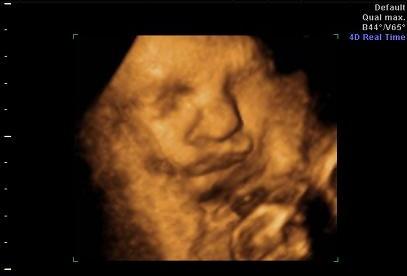

ich seh dich, du mich nicht ... *ätsch* -- 4D US Bildchen

Hab mich heute Nachmittag trotz zunehmender "Rumkugel"- Optik und starker Übelkeit dazu entschlossen, meine Zwerge wiedermal "live" zu besuchen ... leider war Zwerg Nr. 2 nicht so begeistert von der Idee und hat sich hartnäckig versteckt. Aber naja dachte ich zeigs mal her ... hoffentlich funktionierts auch LG dramagie

Ooooh, was für eine Knutschkugel! Und von dem süßen Exemplar kriegt ihr gleich zwei?

achje, was für eine süße schnute dein baby zieht!:)